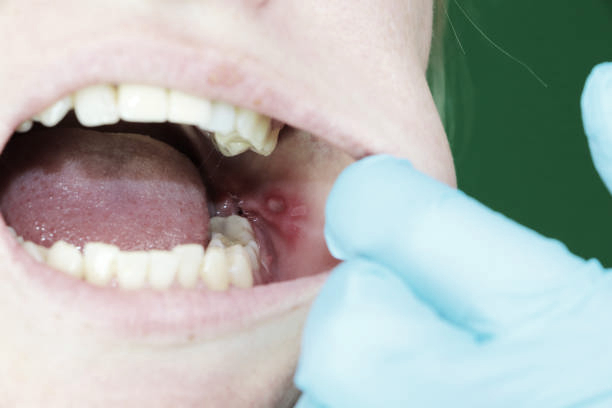

✅심각한 잇몸염증 (치주염)

사랑니 주변의 염증이 심화되어

고름이 차거나 심한 통증이 동반되며

이 상태가 지속되면

잇몸뼈까지 감염될 수 있습니다.

치주염 발생